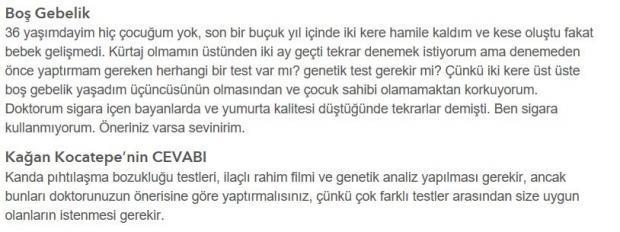

4/21![İki kez hamile kaldım, kese oluştu ama bebek gelişmedi İki kez hamile kaldım, kese oluştu ama bebek gelişmedi]()

İki kez hamile kaldım, kese oluştu ama bebek gelişmedi